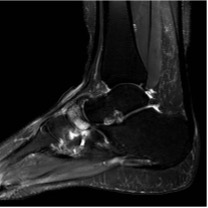

- MRI – for foot pain of unknown origin in the presence of normal radiographs (Figure 8)

Figure 8: T2 MR image showing patchy oedema within the navicular consistent with AVN